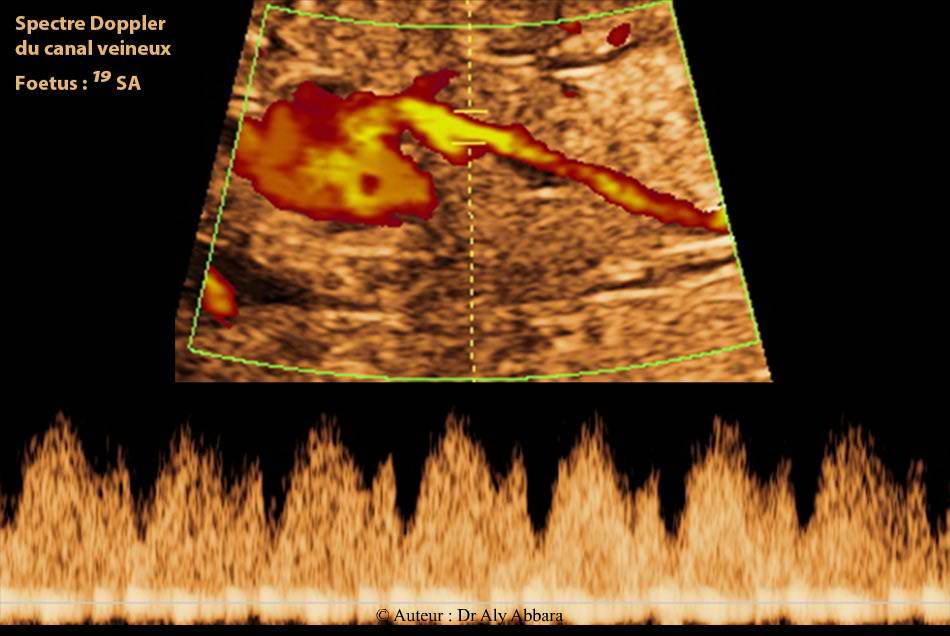

la terminaison du canal veineux à la partie terminale de la veine cave inférieure - spectre Doppler du canal veineux

Images échographiques montrant la terminaison anatomique durant la vie fœtale du ductus veineux (canal veineux, branche de la veine ombilicale gauche) à la partie terminale de la veine cave inférieure

Fœtus de 19 SA dans le cas présent.